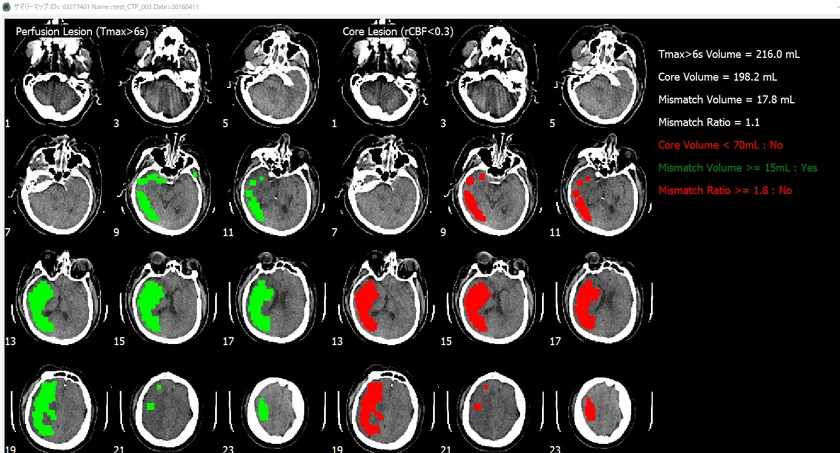

(当製品を使った、CT画像の解析例)

脳画像解析プログラム PMAneo(以下 PMAneo)は、MRI拡散強調画像から低ADC値領域を計測、またMRIまたはCT灌流画像からCBF、CBV、最大遅延時間を計測し、脳血流低下領域の容積およびこれらの差と比を算出、表示する、全自動脳画像解析ソフトウェアです。

PMAneoは、虚血コアと低灌流領域に相当する体積及びミスマッチの自動解析を数分で行う脳画像解析プログラムです。